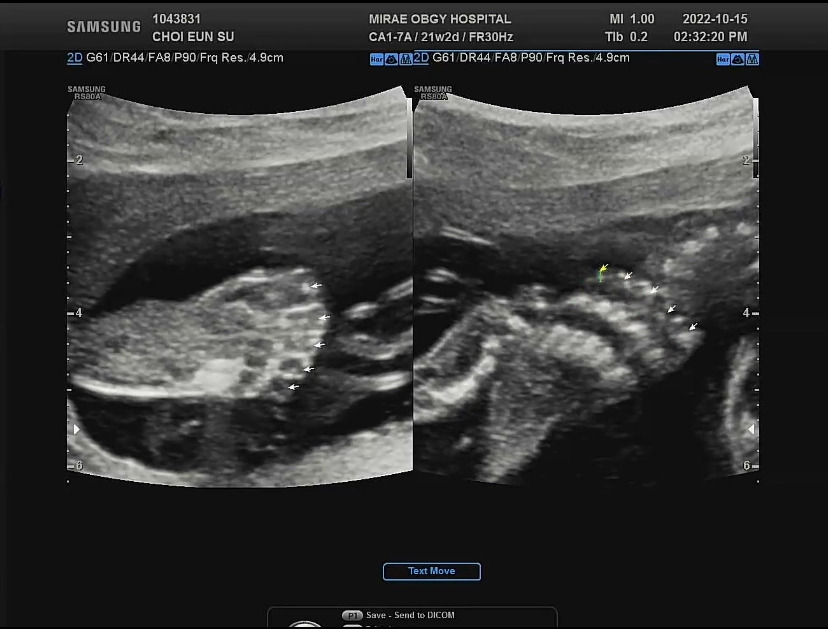

지하철 열심히 타고 병원에 가서 정밀초음파를 했다. 임신 40주의 딱 절반인 20주가 넘어가면서 정밀초음파로 아기의 인중, 귀, 심장(심실과 심방), 심장혈류, 쓸개, 척추, 꼬리뼈, 손발가락, 각종 뼈의 위치, 뇌실의 크기 등등을 볼 수 있었다. 어두운 정밀초음파실에서 10분 정도 정밀초음파를 보고 있자니 어쩐지 졸음이 몰려왔는데 문제는 아기도 졸렸나 보다. 그저 정밀 초음파 시작부터 하품을 시원하게 하며 잠들어버린 아가 덕에 손가락은 보지도 못하고 임신 후 처음으로 아가 주먹을 구경하긴 했지만 그래도 건강하게 잘 크고 있으면 됐다.

12주와 16주차에 한 기형아 검사의 팔로우 업 정도로 혹시 발견하지 못한 선천적 기형이 20주 정밀초음파에서 발견된다고 하기에 (예를 들면 뇌의 이상, 혈류의 이상, 심장의 이상, 척추의 이상 등) 걱정했는데 다행히 무사통과.

정밀초음파에서 처음 본 발가락

그리고 잠들어버린 우리 아가의 옆모습만 한참 구경했다